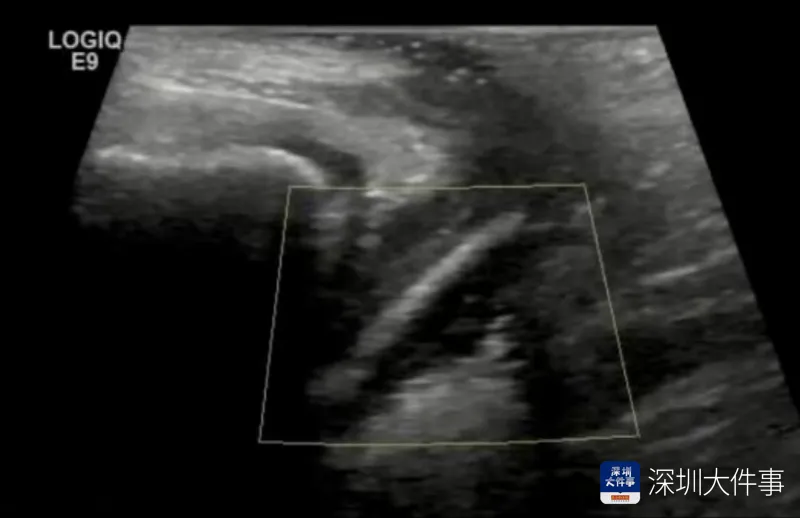

女童母亲介绍,年仅7岁的女儿阴道炎反复数月,其间,用药、清洗、涂抹等治疗均无明显效果。接诊的妇科副主任医师巫旭珍详细询问病史后,结合超声检查,判断并非普通阴道炎,而是阴道内异物引发的炎症。在医生耐心引导下,女童坦言一个月前曾将一支试用装化妆品放入下体私处。

考虑到女童年龄小、生殖道娇嫩,传统操作易造成损伤,医生对其实施阴道内镜检查+异物取出术。术中,医护人员通过内镜清晰看到,女童下体内卡着一支完整的试用装化妆品,随后仅用几分钟便将其完整取出,最大程度保护了儿童生殖器官的完整性与生理功能。